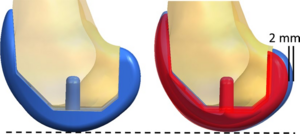

- 3.35 Validation of Osteoarthritis Synthetic Defect Database via Non-rigid Registration